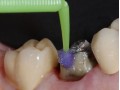

Technika Injection Flowable i technika stempla. Odbudowa…

Flowable Injection Technique – kompozytowa alternatywa dla…